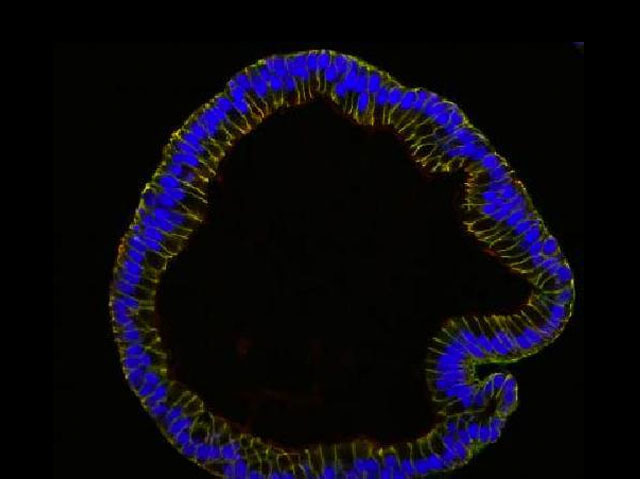

One of the greatest breakthroughs of the last decade is the ability to grow mini-organs, known as organoids, in the laboratory. Under certain conditions, stem cells can self-organise into small structures with recognisable features, providing ideal isolated systems in which to study the function of complex organs and test new drugs. The latest tissues to be investigated using organoids are the fallopian tubes, the ducts connecting the ovaries to the uterus. Both the entry point for ovarian infections and a common site for the development of ovarian cancers, these are critical organs for female health. To replicate the lining of the tubes, researchers produced hollow spheres of cells, as shown here in cross-section, from fallopian tube stem cells. While fallopian cells are difficult to culture with more conventional methods, these organoids may enable a better understanding of a range of gynaecological conditions, from cancer to infertility.